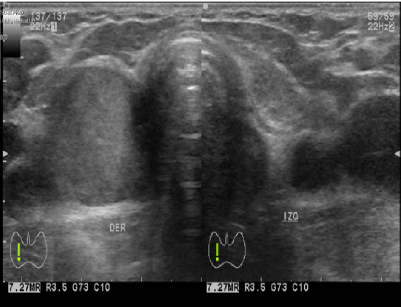

La evaluación ecográfica concluye la presencia de un nódulo en el lecho tiroideo derecho con las siguientes características: heterogéneo, hipoecoico, de bordes bien definidos y dimensiones de 23 x 16 mm (figura 1) sin microcalcificaciones, flujo doppler periférico positivo y ausencia de adenomegalias cervicales (figura 2).

No existen reportes de casos diagnosticados por estudios de imágenes. El ultrasonido con efecto doppler reporta una lesión nodular, sólida, hipoecoica, bien delimitada de tamaño variable e hipervascularizada, características que lo hacen indistinguible de las neoplasias tiroideas comunes. El CT-PET, TAC y gammagrafía tiroidea no son estudios de rutina, y sus hallazgos tampoco permiten distinguirles de otras neoplasias tiroideas15,16.